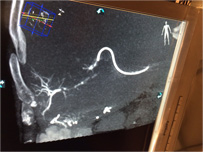

Live 3D MR/CT Roadmap fuses live 2D fluoroscopy on a pre-acquired MR or CT image, which may reveal hidden anomalies and enable real-time motion compensated navigation to support interventional procedures. Live 3D MR/CT Roadmap provides full 3D view for guidance of guidewires, catheters and coils through complex vessel and anatomical structures.

Dynamic 3D Roadmap provides a sustainable 3D roadmap to support interventional procedures. Dynamic 3D Roadmap matches the real-time 2D fluoroscopy images with the 3D-RA reconstruction of the vessel tree. It provides a 3D real-time insight of the advancement of the guide wire, catheter and coils through complex vessel structures. The Unsubtracted 3D Roadmap option reduces subtraction artifacts caused by patient breathing and movements, providing a clear roadmap during abdominal and thoracic interventions.

Live 3D Roadmap allows you to follow the advancement of guidewires, catheters and coils in real-time. It automatically adapts in real-time to changes in C-arm angulation and rotation, table movement, field of view and source-image distance.